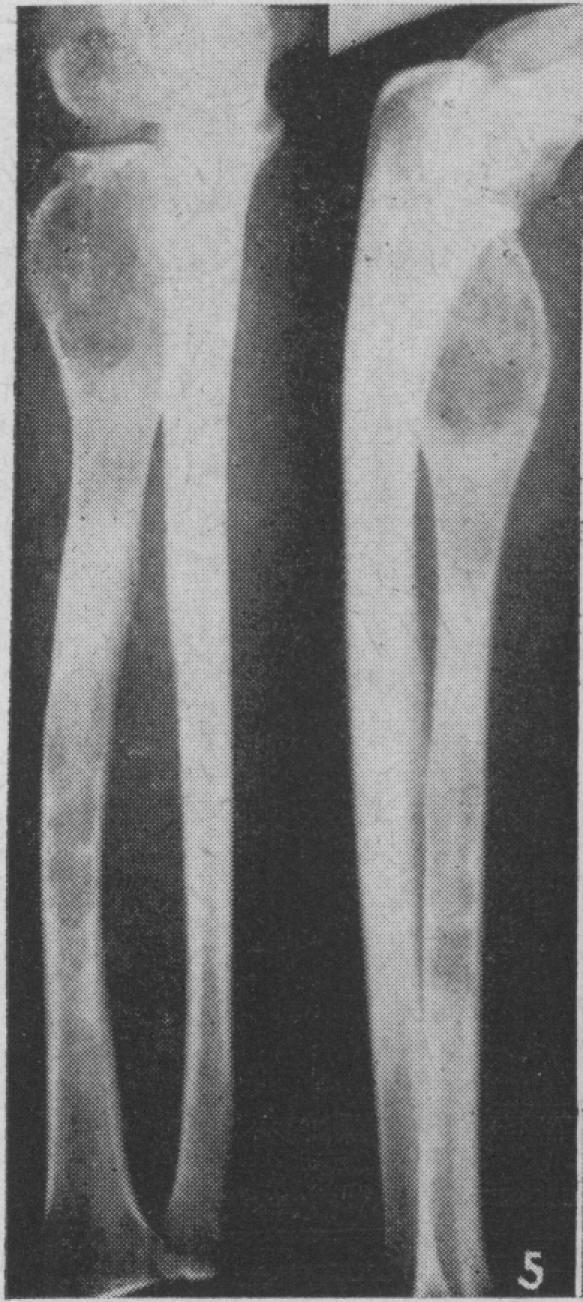

BROOKE H

Can Med Assoc J. 1948 Dec;59(6):555-7.